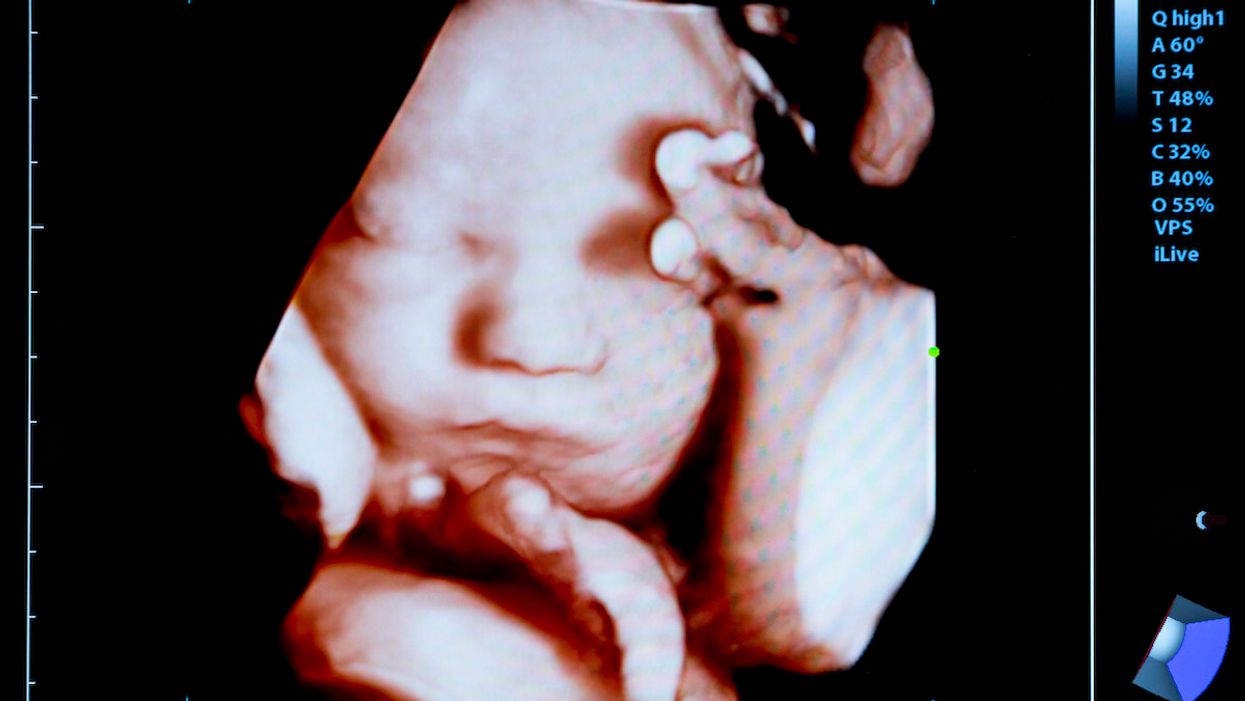

The Supreme Court has opted to leave in place a pro-life Kentucky law that requires women seeking an abortion to see an ultrasound of their unborn children before making the decision to abort.

In a lengthy list of court orders put out Monday morning, the Supreme Court declined to take up the case of EMW Women's Surgical Center v. Meier — a challenge to a Kentucky law that requires women seeking an abortion to be shown an ultrasound of their unborn children before making a final decision.

"We hold that [the law] provides relevant information," the 6th Circuit opinion reads. "The information conveyed by an ultrasound image, its description, and the audible beating fetal heart gives a patient greater knowledge of the unborn life inside her. This also inherently provides the patient with more knowledge about the effect of an abortion procedure: it shows her what, or whom, she is consenting to terminate. That this information might persuade a woman to change her mind does not render it suspect under the First Amendment. It just means that it is pertinent to her decision-making."